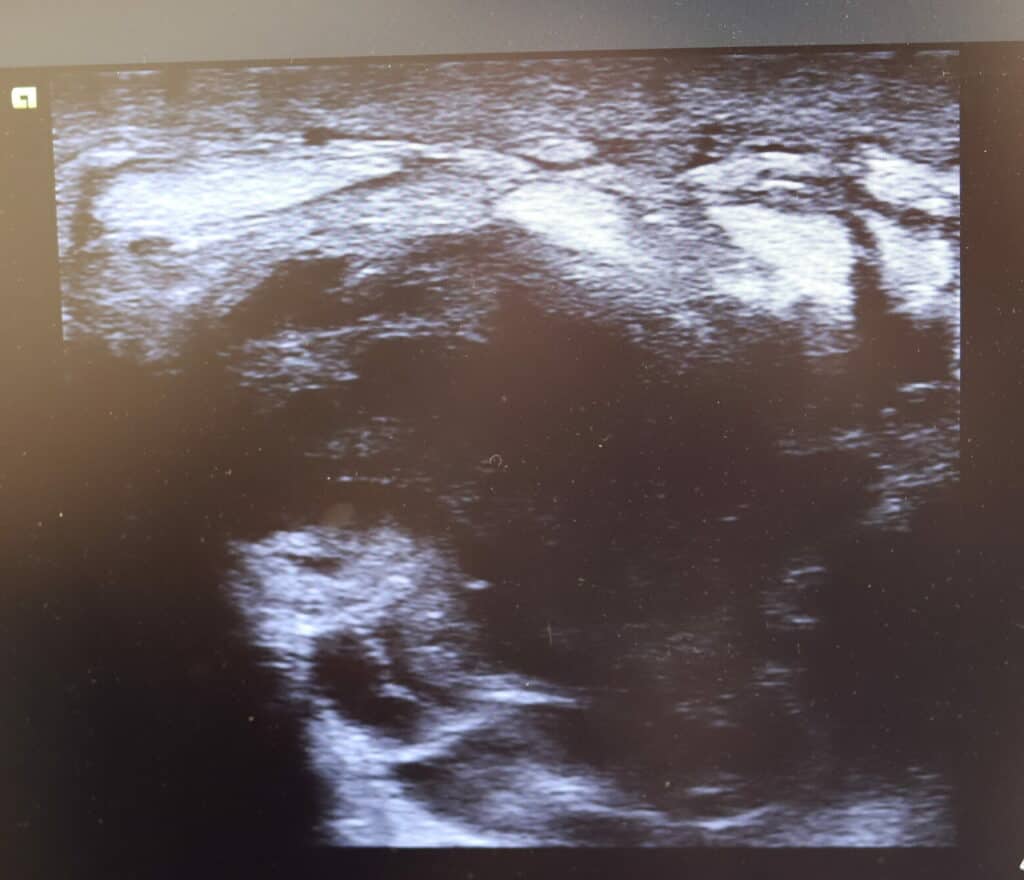

Three more images below from Sirilak Thavornwattana, Pediatric APN, Thailand of serious bruising caused by massage of the lactating breast: